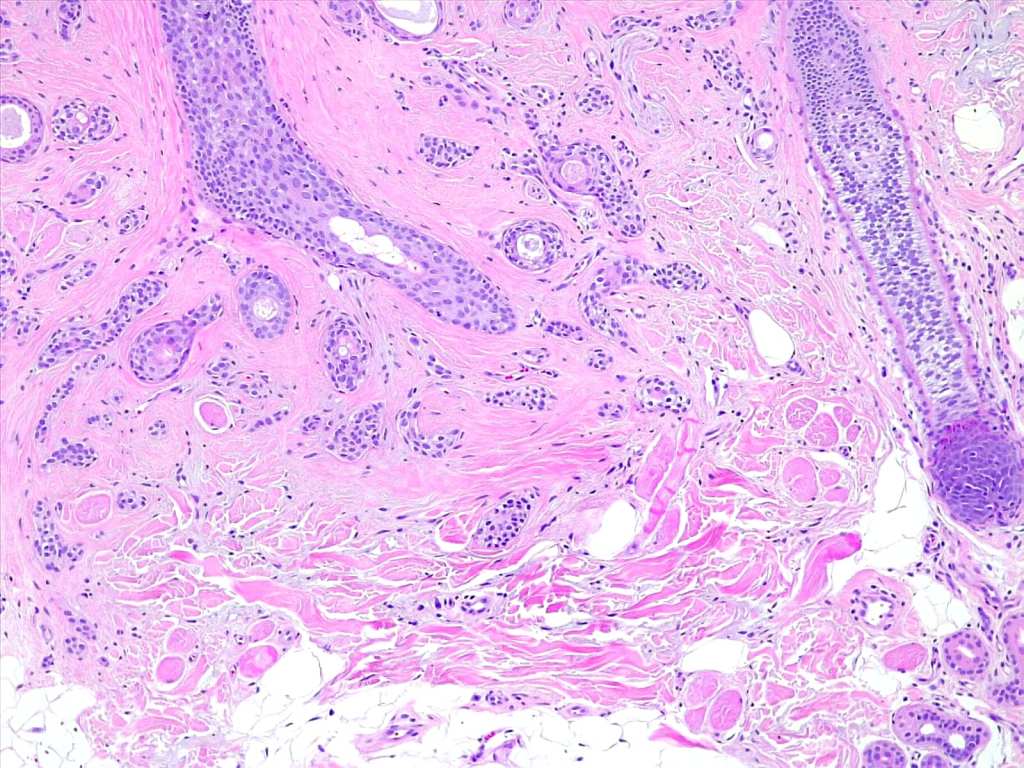

Histological features

•Dermal lesion composed of epithelial stands & ducts dispersed in a fibrous stroma

•Tadpole configuration- ducts with epithelial strands

Intracytoplasmic lumina

•Eruptive milium-like syringoma characterized by a superficial keratin filled cyst associated with an underlying syringoma

Generally speaking, syringoma should not pose any diagnostic difficulties. However shave biopsies can sometimes be problematical. Syringoma differs from desmoplastic trichoepithelioma by the presence of ducts & intracytoplasmic lumina. Microcystic adnexal carcinoma can be distinguished by the presence of keratocysts in the superficial component. In addition, the clinical appearance is quite difference.